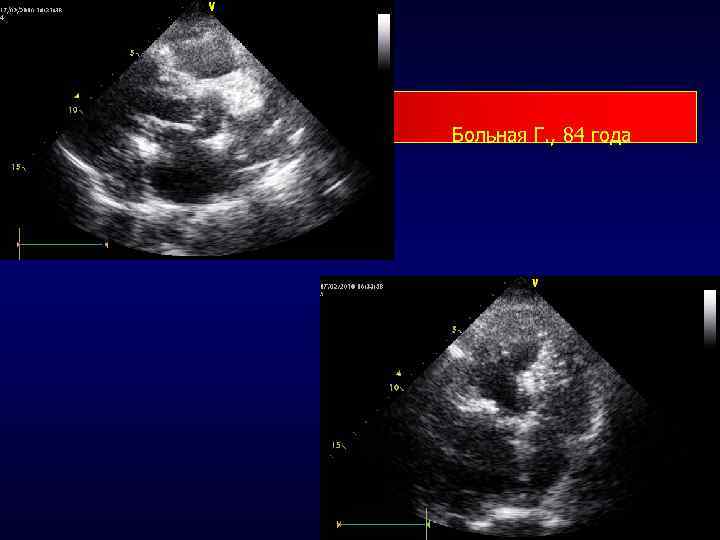

Больная Г. , 84 года

Анатомические образования которые ошибочно могут быть приняты за вегетации • фиброма клапана • миксоматозное поражение створок клапана; • старые вегетации • небактериальный тромботический эндокардит • воспалительные изменения створок при СЗСТ • тромб на створке или на протезе; • артефакт от кальцината или протеза